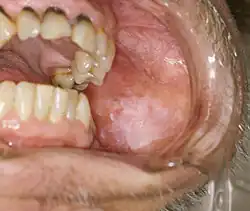

Classic Wickham's striae of non-erosive lichen planus in the left buccal mucosa (left cheek)

Oral lichen planus (also termed oral mucosal lichen planus), is a form of mucosal lichen planus, where lichen planus involves the oral mucosa, the lining of the mouth.[39] This may occur in combination with other variants of lichen planus. Six clinical forms of oral lichen planus (OLP) are recognized:[40]

Reticular

The most common presentation of oral lichen planus (OLP) is characterised by the net-like or spider web-like appearance of lacy white lines, known as Wickham's striae.[41] This is usually asymptomatic. Reticular OLP may progress to the more severe subtypes, such as the erosive form, if left untreated.[2]

Erosive or ulcerative

The second most common form and the most advanced form of oral lichen planus,[41][2] is characterised by oral ulcers presenting with persistent, irregular areas of redness, ulcerations and erosions covered with a yellow slough. This can occur in one or more areas of the mouth. In 25% of people with erosive oral lichen planus, the gums are involved, described as desquamative gingivitis (a condition not unique to lichen planus). This may be the initial or only sign of the condition.[42] Involvement of the dorsum of the tongue might cause an altered sense of taste (dysgeusia).[2]

These types often coexist in the same individual. Oral lichen planus (OLP) tends to present bilaterally as mostly white lesions on the inner cheek,[41] although any mucosal site in the mouth may be involved. Other sites, in decreasing order of frequency, may include the tongue, lips, gingivae, floor of the mouth, and very rarely, the palate.[41]